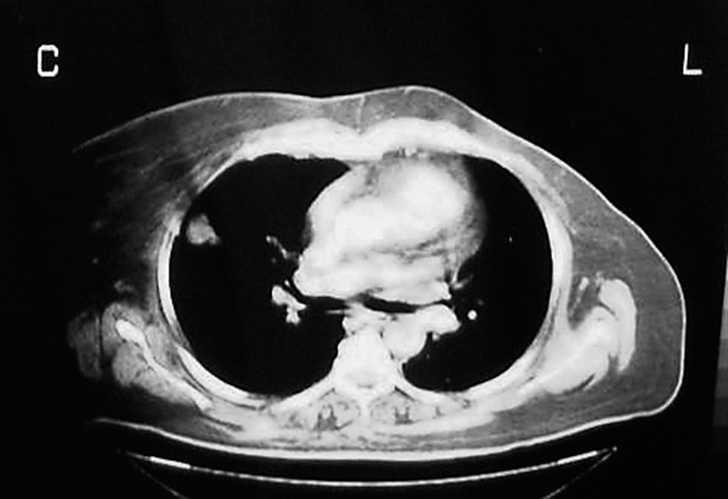

De las cuatro restantes tumoraciones infraescapulares estudiadas, reflejadas en la tabla 1, dos fueron liposarcomas, una fue un lipoma intramuscular y, la última, un hematoma asociado a rotura muscular. En todas ellas se planteó el ED como diagnóstico diferencial. En el caso 6 se halló una tumoración subescapular de unos 10 cm de diámetro en el contexto del estudio de una masa en el muslo derecho, cuya PAAF previa fue indeterminada, y que finalmente correspondió a un liposarcoma multicéntrico metastásico (fig. 7). El caso 7 correspondió a una masa escapular como diseminación de un liposarcoma mixoide en muslo (fig. 8). En el caso 8 se planteó el diagnóstico de elastofibroma por sus características clínicas, descartándolo tras una RMN y llegando al diagnóstico definitivo de lipoma intramuscular tras la resección (fig. 9). El caso 9 corresponde a un varón joven que presentaba una tumoración blanda y elástica en región subescapular de unos 5 cm de diámetro, de tres semanas de evolución y que molestaba con la tos. El estudio por ecografía fue suficiente para llegar al diagnóstico de ruptura muscular y hematoma secundario.

Figura 7. Masa subescapular cuyo diagnóstico final fue de liposarcoma multicéntrico metastásico.